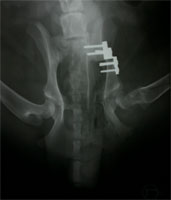

HD vor DBO Operation

Abbildung 2 a: Idealkandidat nach enggefasster Indikationsstellung präoperativ

HD nach DBO Operation

Abbildung 2 b: Der selbe Patient nach DBO. Die Spuren einer erfolglosen Goldakupunktur-Therapie sind zu erkennen.